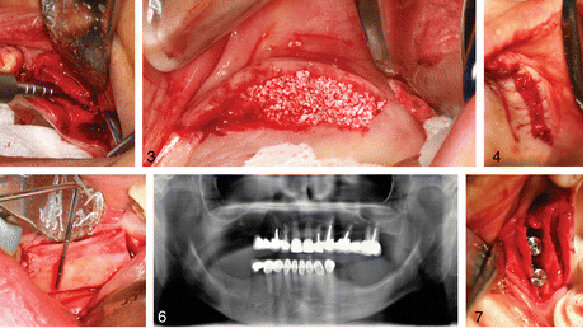

The Journal of Oral Implantology presents a detailed description of the alveolar ridge-split procedure, supplemented by photographs. The alveolar ridge is the bony ridge on both the upper and lower jaws that contains the sockets of the teeth. Establishing an alveolar ridge of proper dimensions has become essential with the advent of root-form endosseous dental implants, the most common type of implants.

The ridge-split procedure described in this article is a form of ridge widening or augmentation. In cases of narrow alveolar ridges, it has proven to be consistently successful. Use of this minimally invasive technique has many advantages in the pre-prosthetic stage of dental implants. Low risk of inferior alveolar nerve injury, less pain and swelling, and no need for a second surgical site as donor are among the benefits.

Because of differences in bone density, the ridge-split technique requires a single surgical stage in the maxilla, or upper jaw, and a two-stage approach in the mandible. The two stages of mandible surgery consist of corticotomy, a bone-cutting procedure, followed by splitting and grafting performed three to five weeks later. The staged approach of the ridge-split procedure has shown a higher implant success rate and better buccal cortical bone preservation.

A practitioner’s experience is an important component of this technique. This form of surgery modifies the configuration of the bone and is usually performed in a closed fashion and uses a tactile sense. The authors emphasize the need for careful manipulation of the thin ridge, knowledge of precise surgical principles, and specialized training.